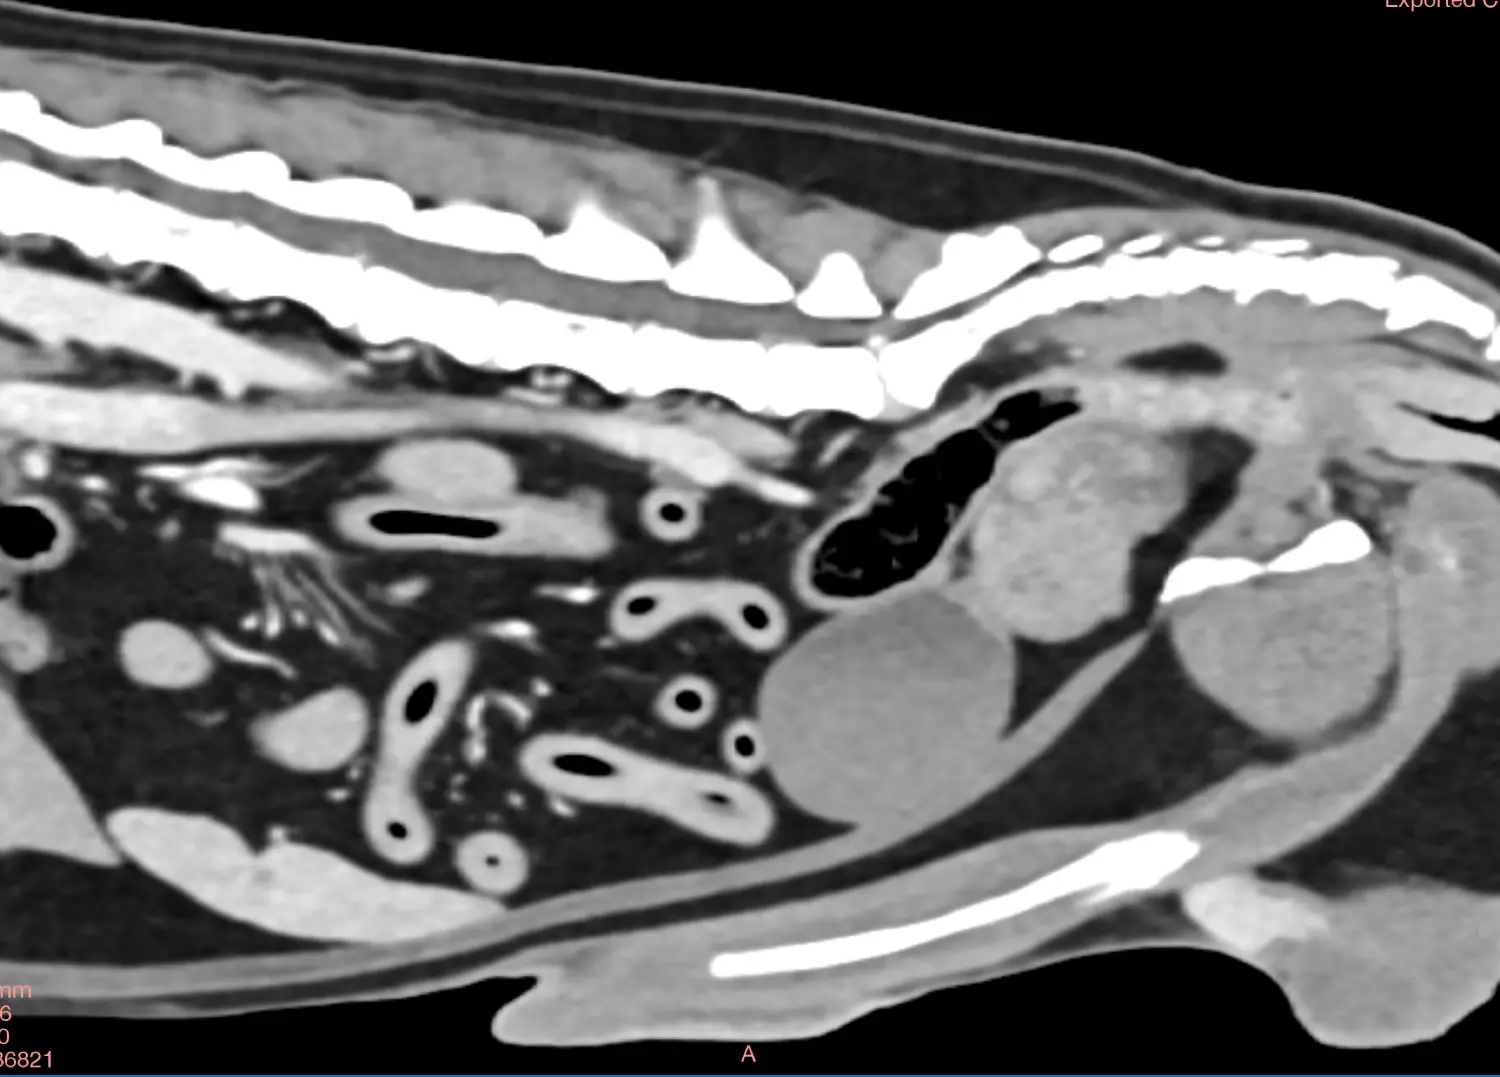

Břicho:

diagnostika nádorových onemocnění, vč. kontroly po jejich léčbě, patologie velkých cév, nemoci jater a žlučových cest, onemocnění ledvin a močopohlavního aparátu. Patologie v oblasti pánevní dutiny - prostata, nádory pánve, fraktury pánve. Diagnostika příčin hromadění tekutiny v břiše – ascitu.